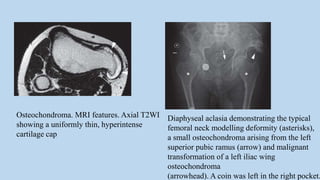

Osteochondroma. MRI features. Axial T2WI

showing a uniformly thin, hyperintense

cartilage cap

Diaphyseal aclasia demonstrating the typical

femoral neck modelling deformity (asterisks),

a small osteochondroma arising from the left

superior pubic ramus (arrow) and malignant

transformation of a left iliac wing

osteochondroma

(arrowhead). A coin was left in the right pocket.

Osteochondroma. MRI features.Axial T2WI showing a uniformly thin, hyperintense cartilage cap Diaphyseal aclasia demonstrating the typical femoral neck modelling deformity (asterisks), a small osteochondroma arising from the left superior pubic ramus (arrow) and malignant transformation of a left iliac wing osteochondroma (arrowhead). A coin was left in the right pocket.